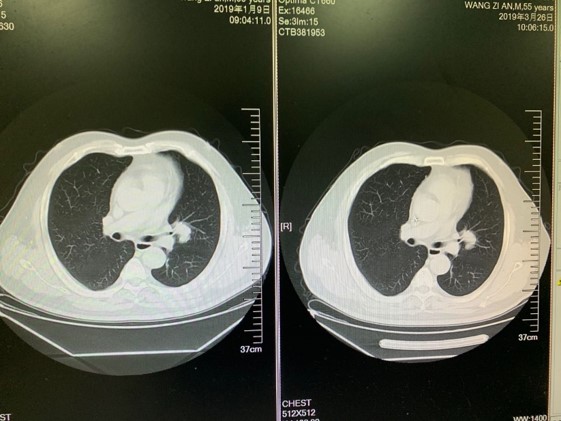

2018.3月复查胸部CT示,左肺多发结节,考虑肺转移。

三线治疗SD6个月

全服CT显示疾病稳定